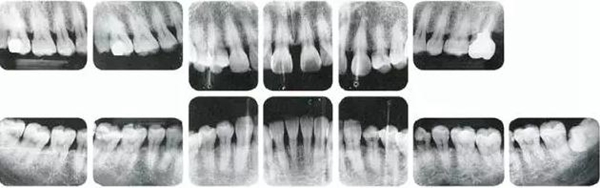

●參考病例② 25歲女性

25歲女性。菌斑控制狀態(tài)不好。齦溝除磨牙處外全在3mm以下,X光照片上左上、右下、左下的第一磨牙上有垂直性骨吸收。這個(gè)病例是參考病例①10年前的狀態(tài),是典型的侵襲性牙周炎局部型。